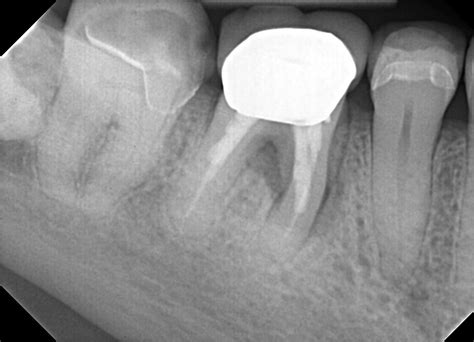

1. Diagnosis and Anesthesia: Your dentist will take X-rays to assess the extent of the infection. Local anesthesia is administered to ensure you do not feel pain during the treatment.

3. Cleaning and Shaping: The infected pulp is carefully removed using specialized dental instruments. The canals are then cleaned, disinfected, and shaped to receive a filling material.

4. Filling and Sealing: The hollowed-out canals are filled with a biocompatible material called gutta-percha, which is cemented into place.

5. Restoration: Because a tooth that has undergone an Rct of teeth may become brittle, a crown or permanent filling is usually placed to protect it and restore its original functionality.